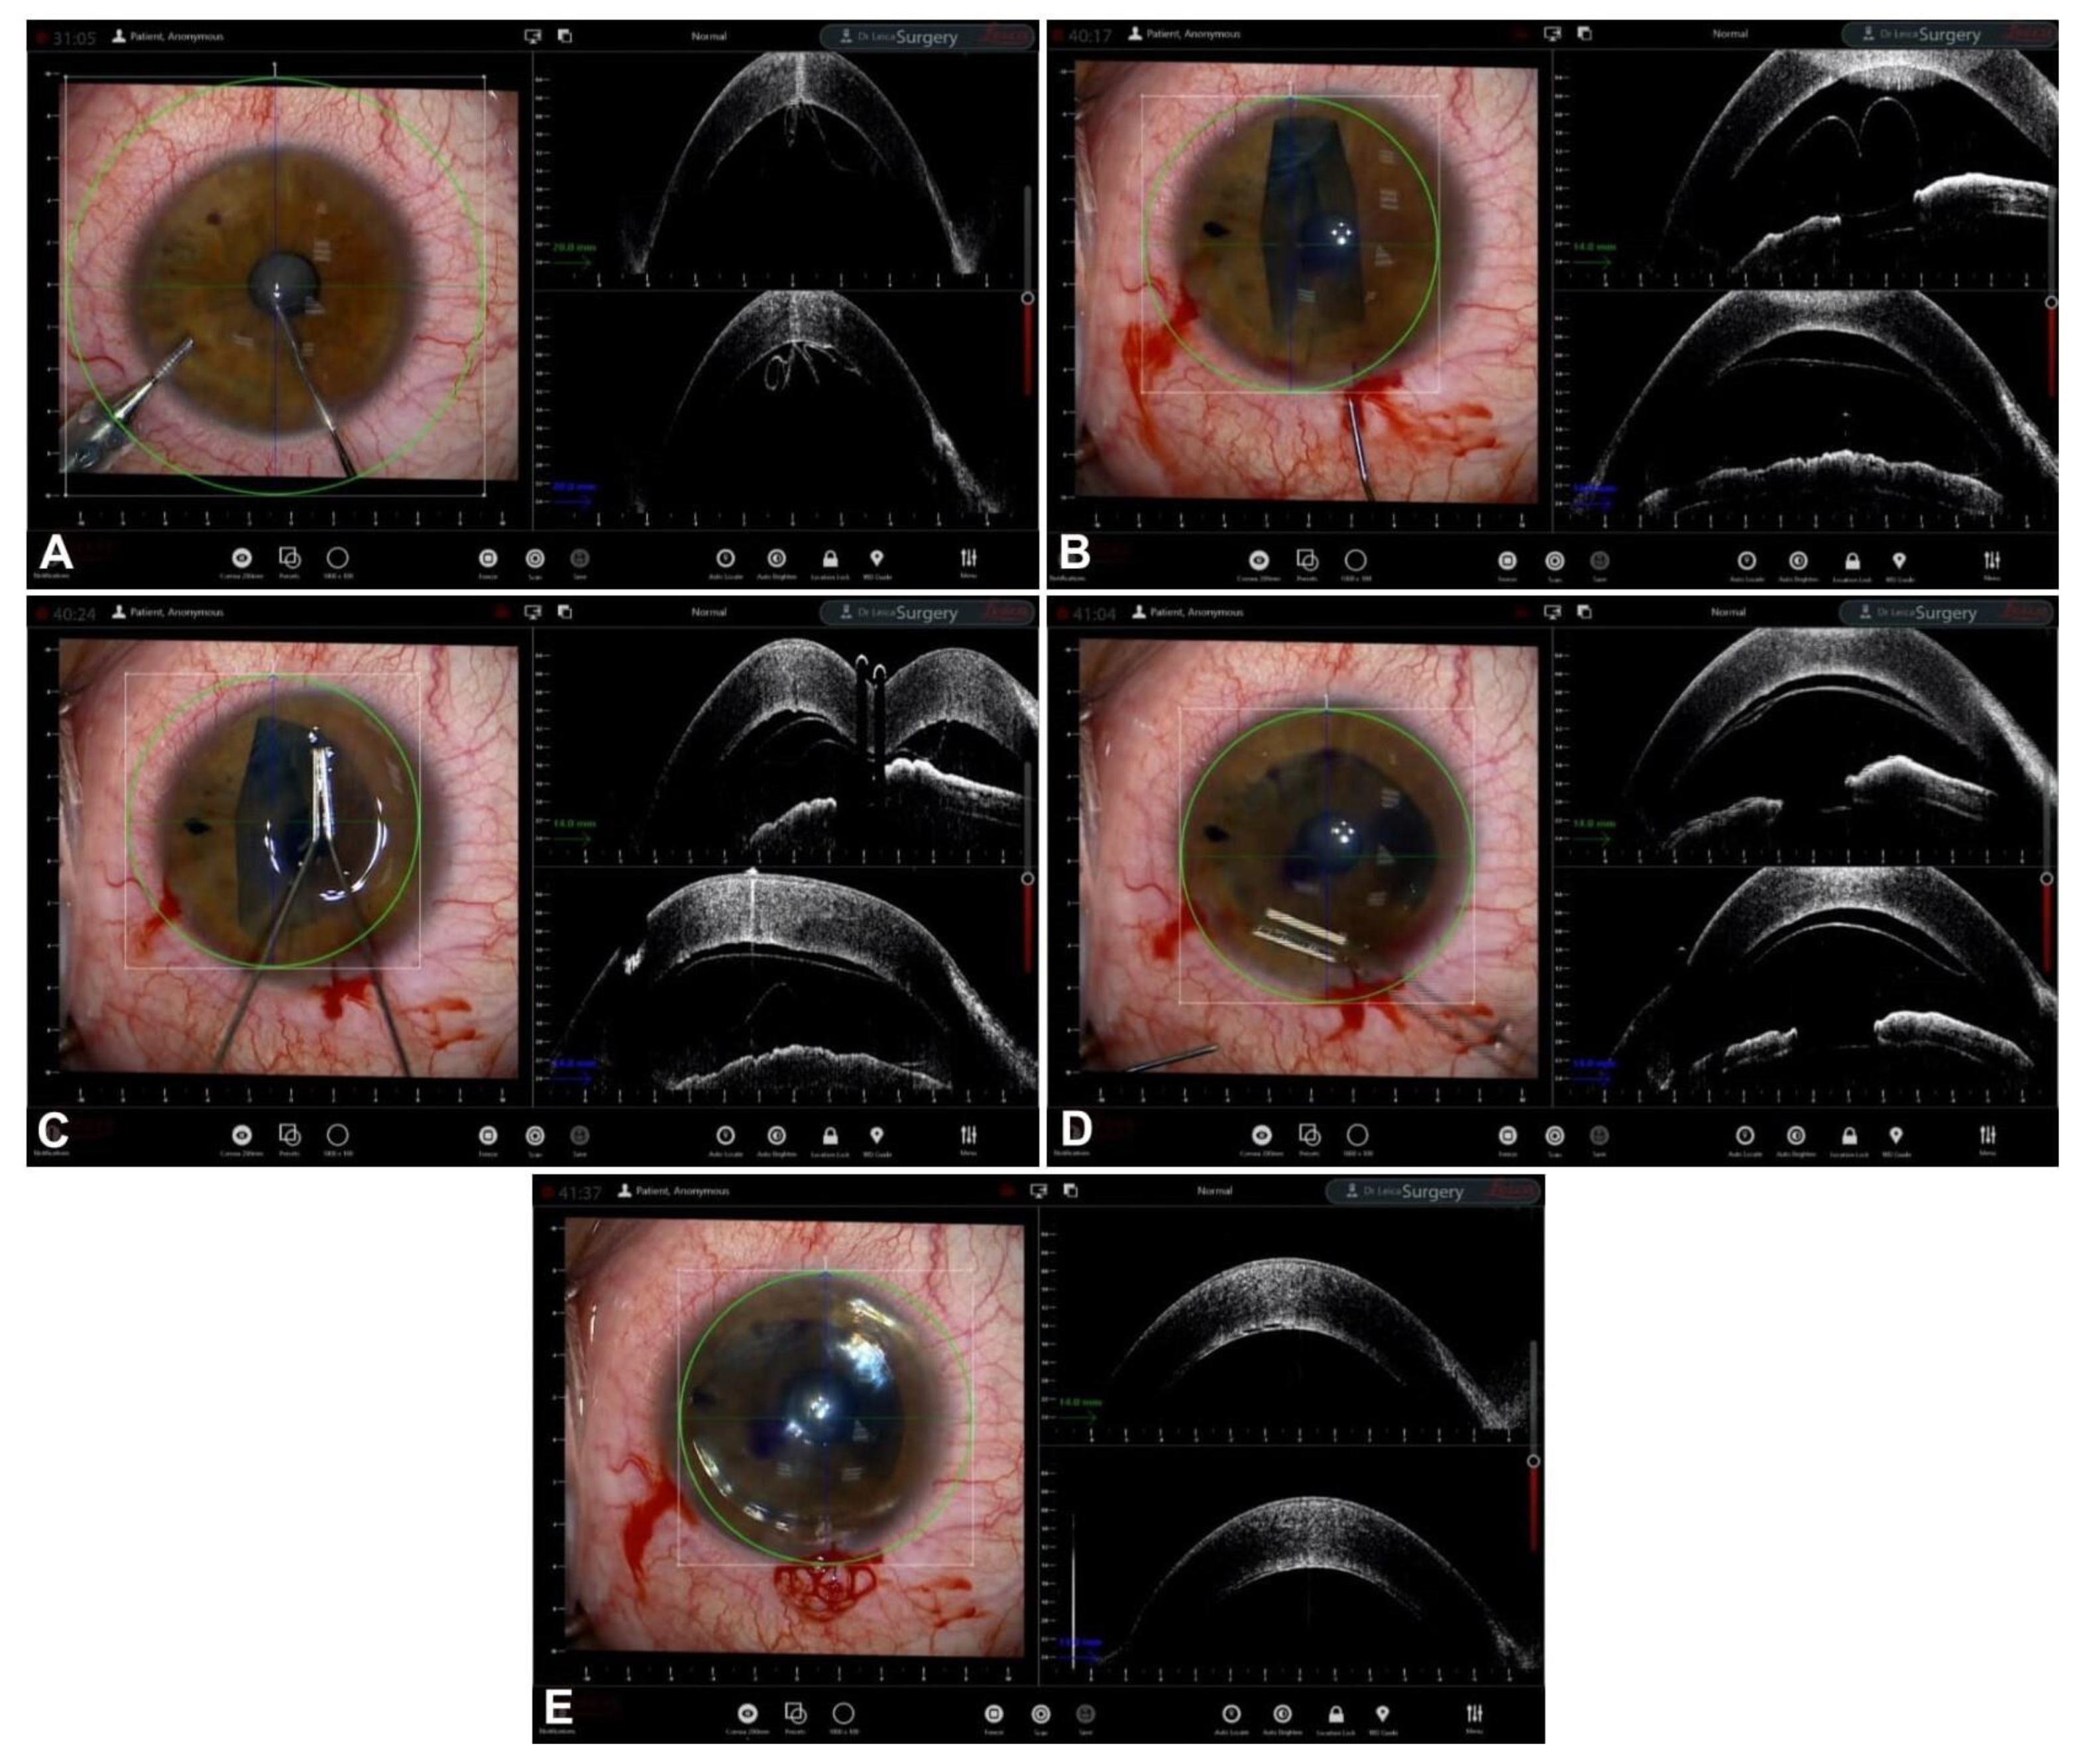

Guiding Big-Bubble Deep Anterior Lamellar Keratoplasty (BB-DALK)

3. Guiding Manual Stromal Dissection DALK

- Santorum, P.; Yu, A.C.; Bertelli, E.; Busin, M. Microscope-Integrated Intraoperative Optical Coherence Tomography–Guided Big-Bubble Deep Anterior Lamellar Keratoplasty. Cornea 2021, 41, 125–129. [Google Scholar] [CrossRef]

- Scorcia, V.; Busin, M.; Lucisano, A.; Beltz, J.; Carta, A.; Scorcia, G. Anterior Segment Optical Coherence Tomography–Guided Big-Bubble Technique. Ophthalmology 2013, 120, 471–476. [Google Scholar] [CrossRef] [PubMed]

- Myerscough, J.; Friehmann, A.; Busin, M.; Goor, D. Successful Visualization of a Big Bubble during Deep Anterior Lamellar Keratoplasty using Intraoperative OCT. Ophthalmology 2019, 126, 1062. [Google Scholar] [CrossRef] [PubMed]

- Steven, P.; Le Blanc, C.; Lankenau, E.; Krug, M.; Oelckers, S.; Heindl, L.M.; Gehlsen, U.; Huettmann, G.; Cursiefen, C. Optimising deep anterior lamellar keratoplasty (DALK) using intraoperative online optical coherence tomography (iOCT). Br. J. Ophthalmol. 2014, 98, 900–904. [Google Scholar] [CrossRef] [PubMed]

- Au, J.; Goshe, J.; Dupps, W.J.; Srivastava, S.K.; Ehlers, J.P. Intraoperative Optical Coherence Tomography for Enhanced Depth Visualization in Deep Anterior Lamellar Keratoplasty from the PIONEER Study. Cornea 2015, 34, 1039–1043. [Google Scholar] [CrossRef]